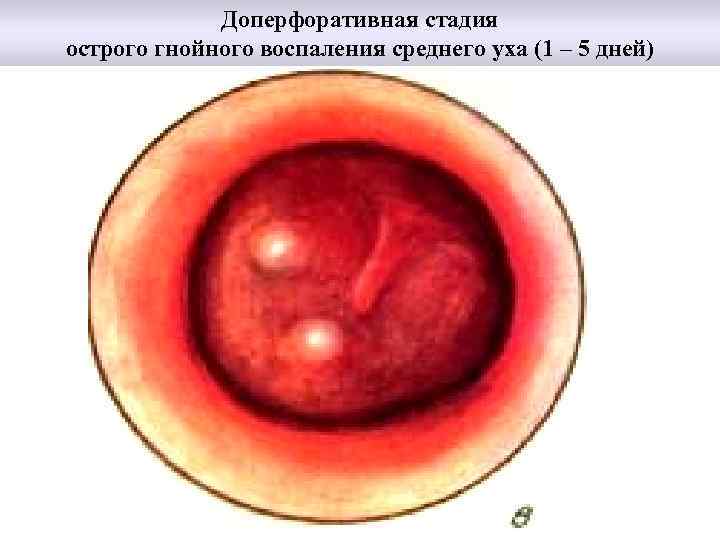

Доперфоративная стадия острого гнойного воспаления среднего уха (1 – 5 дней)